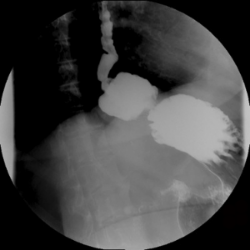

-Tránsito esófago-gastro-duodenal (estudio con contraste baritado o hidrosoluble): Consiste en ingerir bebida con contraste y, posteriormente, realizar una radiografía para evidenciar parte del estómago en la cavidad torácica.